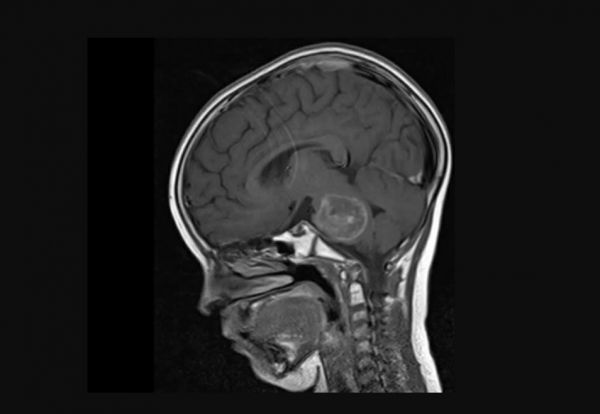

Στεφανιαία τομή Μαγνητικής Τομογραφίας ασθενούς 6 ετών με ΔΔΓΓ

Η Μαγνητική Τομογραφία του Εγκεφάλου αποτελεί τη μέθοδο με την καλύτερη απεικονιστική δυνατότητα. Αποτελεί μια διαγνωστική διαδικασία που χρησιμοποιεί ένα συνδυασμό μεγάλων μαγνητών, ραδιοσυχνοτήτων και υπολογιστή για την παραγωγή λεπτομερών εικόνων οργάνων και δομών μέσα στο σώμα.

Η μαγνητική τομογραφία παρέχει μεγαλύτερη ανατομική λεπτομέρεια από την αξονική τομογραφία και κάνει καλύτερη διάκριση μεταξύ των όγκων, του οιδήματος που σχετίζεται με τους όγκους και τον φυσιολογικό ιστό.